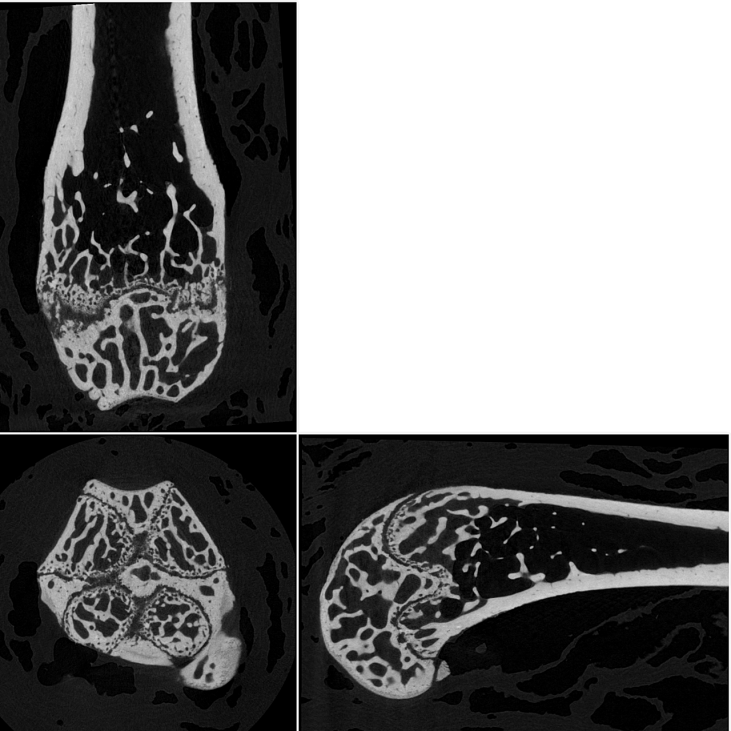

1. Volume rendered 3D model of a femur with color-codedrepresentation of the trabecular thickness, scanned at 2.8 umpixel size

8. Orthogonal slices through a mouse femur, scanned at 2.8 umvoxel size.